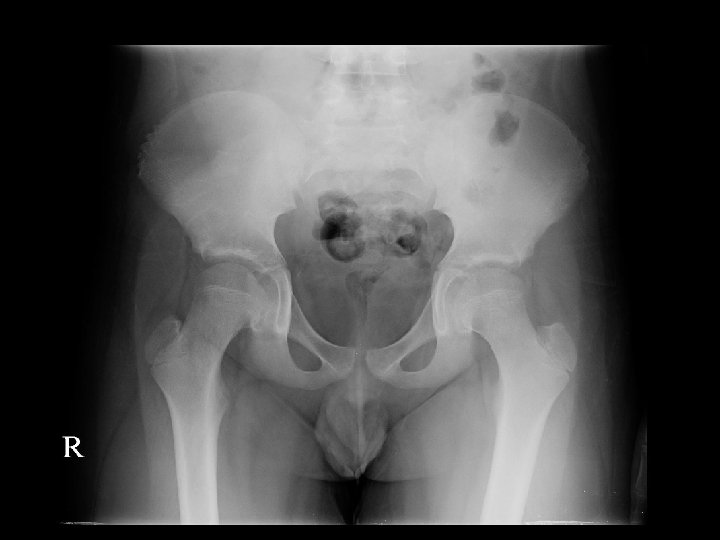

Bone Scan v. Bone scan (17/08/52) v. Bone lesion at skull is corresponding with multiple geographic lytic lesions without sclerotic rim and some blastic lesions in diploic space of bilateral parietal bone, likely bone metastases. Bone lesion at C 2 vertebral body, pelvic rim, right acetabulum, head, proximal, mid shaft and distal right femur, likely due to bone metastases as correlated with lytic lesion seen on PET/CT.

Management v. Due to PET/CT found multiple small hypermetabolic poorly osteolytic and non-osteolytic lesion, suspected bone metastases consult orthopaedics 23/7/52 Excision Bone at Right iliac, right proximal tumor

Pathological report of Bone Biopsy

Pathology Report v. Right iliac bone biopsy (23/07/52) v. Section show fragments of bony tissue and marrow element. Few pieces of bone reveal proliferation of blood vessels with occasionally lined by round to spindleshaped cells. Cells have round nuclei, fine chromatin, visible nucleoli v. Immunohistochemistry: epithelioid hemangioendothelioma

Pathology Report v. Right proximal femur : no definite vascular tumor

v. Impression : Gorham disease